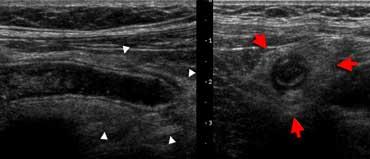

Mỡ viêm trên siêu âm. Hình ảnh toàn cảnh vùng bụng trước cho thấy một vùng mỡ mạc nối tăng âm, không đè xẹp được (mũi tên đỏ). So sánh với độ âm vang của mỡ bụng hoặc mỡ dưới da bình thường (mũi tên xanh). Bệnh nhân này được chẩn đoán nhồi máu mạc nối.

Mỡ viêm

Mỡ viêm có đặc điểm tăng âm, chiếm chỗ và không đè xẹp được trên siêu âm.

Cùng bệnh nhân trên. CT không tiêm thuốc cản quang cho thấy một vùng mô mỡ tăng tỷ trọng nhẹ (đầu mũi tên) ở góc phần tư trên phải. So sánh với mỡ dưới da bình thường có tỷ trọng thấp. Chẩn đoán: nhồi máu mạc nối.

Mỡ viêm biểu hiện dưới dạng dải mỡ (fat-stranding) trên CT. Mỡ viêm là dấu hiệu hữu ích giúp xác định vị trí và bản chất của tổn thương.

Theo nguyên tắc, cơ quan hoặc cấu trúc nằm ở trung tâm hoặc gần nhất với vùng mỡ viêm chính là nguyên nhân gây viêm.

Lâm sàng nghi viêm ruột thừa. Siêu âm chỉ phát hiện một lượng nhỏ dịch cổ trướng. Chọc dò chẩn đoán (mũi tên chỉ đầu kim) cho thấy dịch máu. Ở phụ nữ, phát hiện này rất nghi ngờ thai ngoài tử cung (EUG).

Cổ trướng

Người tình nguyện khỏe mạnh không có lượng dịch tự do trong ổ phúc mạc có thể phát hiện được, ngoại trừ một lượng nhỏ dịch tình cờ ở túi cùng Douglas ở phụ nữ trong độ tuổi sinh sản.

Sự hiện diện của cổ trướng là dấu hiệu không đặc hiệu của bệnh lý ổ bụng, cho thấy ‘có điều gì đó bất thường’.

Có thể cân nhắc thực hiện chọc dò dịch cổ trướng dưới hướng dẫn siêu âm để xác định bản chất dịch: dịch phản ứng vô khuẩn, mủ, máu, nước tiểu hay dịch mật.